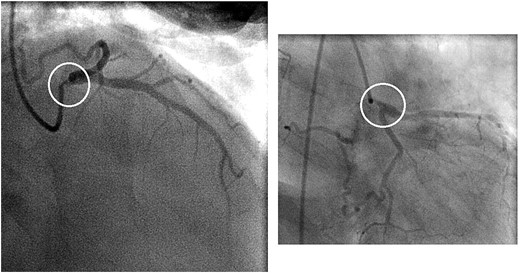

A 46-year-old female presented with recurrent chest pain radiating to the left arm accompanied by dyspnea. She was a non-smoker with no significant past medical history. Physical examination, laboratory results, chest X-ray, and electrocardiogram were all normal. Transthoracic echocardiography showed normal valvular function, a left ventricular ejection fraction of 63%, and mildly impaired diastolic function. Multislice computed tomographic coronary angiography revealed sub-total occlusion of the left main coronary artery, starting at the ostium and extending 5 mm distally (Fig. 1). Cardiac catheterization revealed a right-dominant coronary circulation, with a 90% stenosis in the ostial and proximal shaft of the left main coronary artery, with no other lesions detected (Fig. 2).

Preoperative coronary angiogram showing a 90% stenosis in the ostial and proximal shaft of the left main coronary artery (circles)